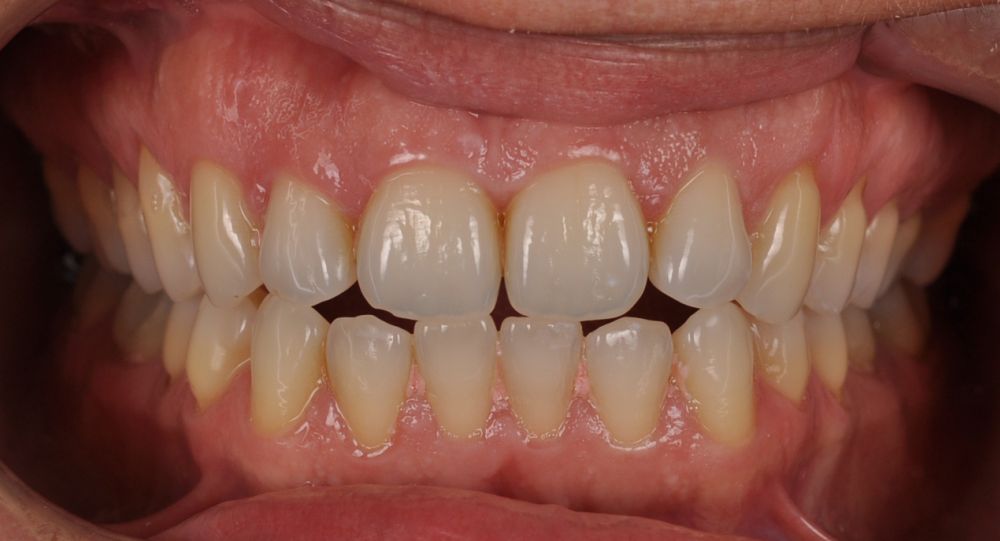

El día de la colocación de las estructuras, se arenó el interior de las coronas dentosoportadas con óxido de aluminio de 50 m y fueron cementadas con cemento de resina Multilink Ò. El puente implantosoportado se atornilló al torque indicado (20Nw) (Figuras 14, 15, 16 y 17).

En el seguimiento a 4 años tras la colocación de la prótesis definitiva, no se observaron complicaciones mecánicas ni biológicas. La paciente continúa libre de enfermedad y con una correcta adaptación al tratamiento rehabilitador implantosoportado (Figura 18).